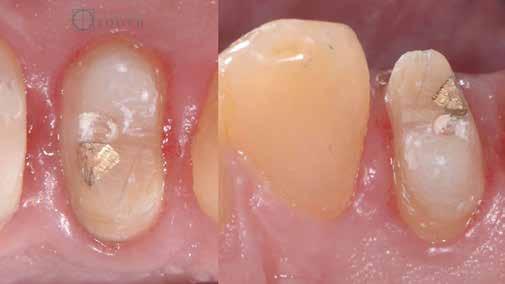

A mindennapi gyakorlatban gyakran találkozunk súlyos fogszuvasodással. A fogorvosnak mindig kihívást jelent a döntés, hogy kihúzzuk és implantátummal pótoljuk, vagy megmentjük a fogat, de kétséges a hosszú távú prognózis. Számos cikkből tudjuk, mint például Seltzer és Kim (Comparison of Long term survival of implant and endodontically treated teeth J Dent Res 93(1):19-26, 2014) cikke, hogy a fogak viszszanyerése jobb megoldás, különösen a fiatalabb betegeknél. A kirakós hiányzó kulcsa az általános fogorvos számára gyakran a maradó fogazat jó biomechanikai értékelése. Az endodontikusan kezelt fogak kudarcainak többsége valójában mechanikai hibákhoz, például repedéshez és töréshez kapcsolódik. A maradó fogszerkezet gondos biomechanikai értékelése, valamint a mechanikai teljesítményt javító technikákra való összpontosítás a legfontosabb a hosszú távú eredmény keresésében. A szerző praxisában a vertikális pre-

parálás és a minimális megközelítés kombinációja, valamint az ortodontikus extrúzió alkalmazása a restauratív fogászatban megváltoztatja a helyzetet, amint azt a következő eset is mutatja.

Egy 35 éves kaukázusi férfi páciens az 1.4-es fog (felső első premoláris) törése miatt kereste fel rendelőnket, a törés ferde volt. A sérült fogak helyreállítása során az egyik legfontosabb lépés a megmaradt fogazat biomechanikai értékelése . Egy hiba ebben a fázisban káros a hosszú távú eredményre . A legtöbb repedést például a fogüregek helyreállító fogászathoz való helytelen előkészítése okozza. Ugyanígy a fennmaradó szerkezet helytelen értékelése idővel mechanikai okokból bekövetkező meghibásodáshoz vezethet.

2. ábra: Az okkluzális nézet a fogszerkezet mennyiségét mutatja, a röntgenfelvételen az 1.5. fogon II. osztályú szuvasodás is látható. Még ha lehetséges is ezeket az eseteket koronahosszabbítással kezelni, a végeredmény átlagosan nem kielégítő. A ferrule gyógyulása korlátozott, és olyan parodontális szövődményekkel is találkozunk, mint a fekete háromszögek, a szomszédos fogak gyökérkitettsége. A fogszabályozó extrúzió sokkal előnyösebb.

4. ábra: A fogszerkezet helyreállítása és a fogrestaurációs komplexum ellenálló képességének javítása érdekében ortodontikus extrúziót végeztek a szomszédos fogakra ragasztott drót és egy egyszerű rugalmas ligatúra segítségével.

5. ábra: Az extrudálás nyomon követése néhány hét múlva. Az extrúzió végén a lágyrészek kisebb mértékű újrakontúrozása történt. A szerző általában fibrectomia nélkül végzi az extrúziót, és az extrúzió végén a lágyrészek újrakontúrozását végzi.

6. ábra: A fog az extrúzió és a függőleges preparálás után. A függőleges preparáció a legjobb preparátum a fog szerkezetének megőrzése szempontjából, különösen akkor, ha minimálisan invazív megközelítéssel alkalmazzák. A szerző egy módosított vertikális technikát alkalmaz, amely nagyobb hangsúlyt fektet a pericervikális dentin fenntartására.

7. ábra: A bukkális szerkezet összehasonlítása extrudálás előtt/után . A maradék fogazati struktúra okklusális terhelése most sokkal kedvezőbb a hosszú távú eredmény szempontjából .

8. ábra: Ideiglenes eltávolítás. 9. ábra: Még a szájpadlásfalon is volt fogazati struktúra-gyarapodás. A szájpadlásfal mintegy 35%-a már szilárd fogazati struktúrán van. Ez a jobb biomechanika miatt sokkal jobb eredményt tesz lehetővé a későbbi restauráció számára.

10. ábra: A cirkónium-dioxid korona cementálása üveg-ionomer cementtel . Ezzel a megközelítéssel nyilvánvaló, hogy a ferrule menynyisége a szomszédos fogakra gyakorolt bármilyen komplikáció nélkül nyert. A parodontális apparátus valójában érintetlen. Nincsenek fekete háromszögek, nincs a szomszédos fogak gyökérkitettségének kockázata. Már a szülés napján megvan a papilla, amely kitölti az intraproximális tereket. A nyert ferrule mennyisége hatalmas. A bukkális falon könnyen felismerhetjük, hogy az egész fal már szilárd fogazati struktúrán van, a palatális falon pedig az ajánlott 1-1,5 mm-nél jóval több. A függőleges preparálással szintén könnyen meg tudjuk tartani a visszanyert fogszerkezet mennyiségét , különösen a pericervikális dentin területén, ami a legfontosabb a hosszú távú eredmény szempontjából.